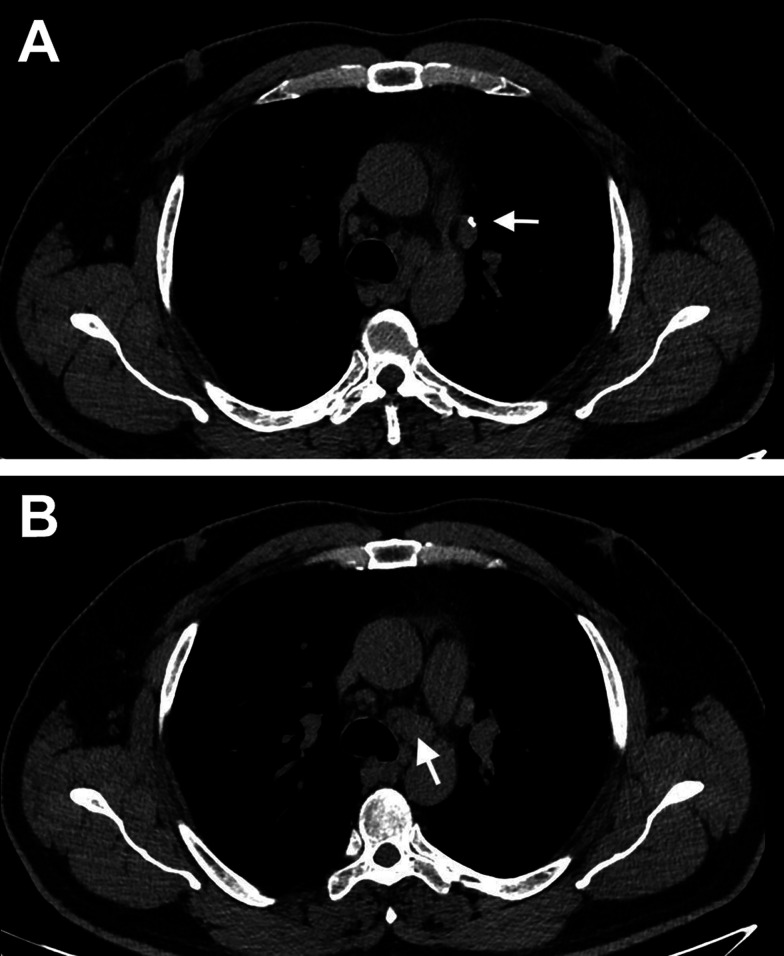

矽肺病是一种因吸入结晶化合物而引起的纤维化呼吸系统疾病。特别是在所有使用二氧化硅的行业中,如喷砂、石凳制造、陶瓷、珠宝和玻璃生产,都应该考虑到这一点。Sjögren综合征(SS)是一种缓慢进展的全身性自身免疫性疾病,其特征是慢性淋巴细胞侵袭外分泌腺和腺外组织,并伴有一系列全身性症状。职业二氧化硅暴露已知与自身免疫性疾病有关,如系统性硬化症和系统性红斑狼疮。本文介绍了一个陶瓷工人Sjögren综合征的病例。

Silicosis is a fibrotic respiratory disease caused by inhalation of crystalline compounds. In particular, it should be taken into account in all professions where silica is used, such as sandblasting, stone bench manufacturing, ceramics, jewelry and glass production Sjögren's syndrome (SS) is a slowly progressive systemic autoimmune disease characterized by chronic lymphocytic invasion of exocrine glands and extraglandular tissues, accompanied by a series of systemic symptoms. Occupational silica exposure is known to be associated with autoimmune diseases such as systemic sclerosis and systemic lupus erythematosus This manuscript presents a case of Sjögren's syndrome in a ceramic worker.